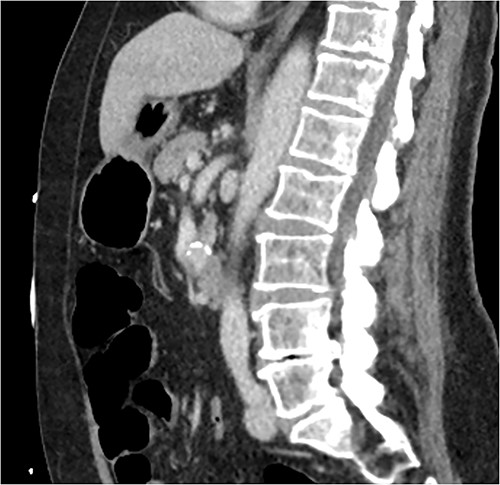

A multiphase CT of the pancreas had unexpected findings. There were no pancreatic masses on the arterial and portal phase study, and no paraaortic or mesenteric lymphadenopathy. The abnormal calcification seen on the previous study corresponded to a dilated vessel along the superior margin of the pancreatic body. This dilated vessel was an abnormal communication between a tortuous ecstatic gastroduodenal artery and the first branch of the SMA, a Buhler’s arc communication. The celiac axis origin was narrowed >90%. No other suspicious solid organ mass lesion was identified. Soft tissues were unremarkable (Figs 5–8).

Multiphase CT pancreas, sagittal view: abnormal communication between the CA and the SMA. The celiac axis is markedly narrowed, >90%.